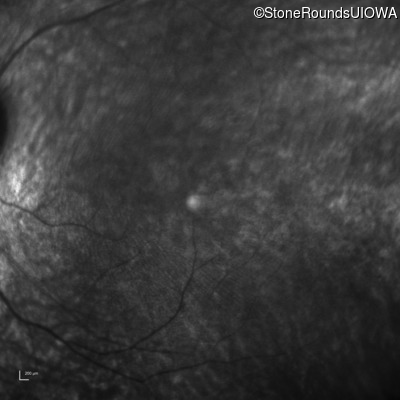

Infrared Fundus Photograph - Right - 20/200 sc

Exemplar